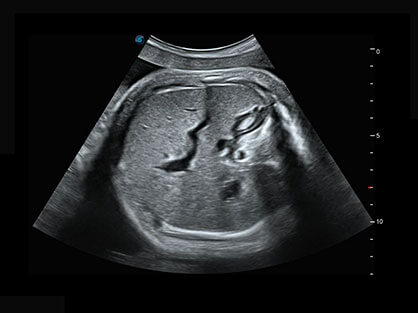

作为P系列家族成员之一,P40 Plus采用哈哈体育官网高端超声系统平台——极光,并以时尚秀丽、小巧灵动的外观设计绽放出灵动之韵、科技之美。高端平台的使用保证了P40 Plus优质的基础图像;完备的高级功能可满足您全身应用的基本需求;丰富的探头配置、多样的高级4D成像及分析软件为您日益增多的妇产应用需求提供丰富的诊疗方案。

结合哈哈体育官网超宽频带探头技术优势,能够更好地获得高分辨力与高穿透力的平衡,保证图像质量,为临床诊断保驾护航。

微米成像技术提升了对组织斑点噪声信号的抑制能力,并进一步强化边界信息,从而获得清晰图像。